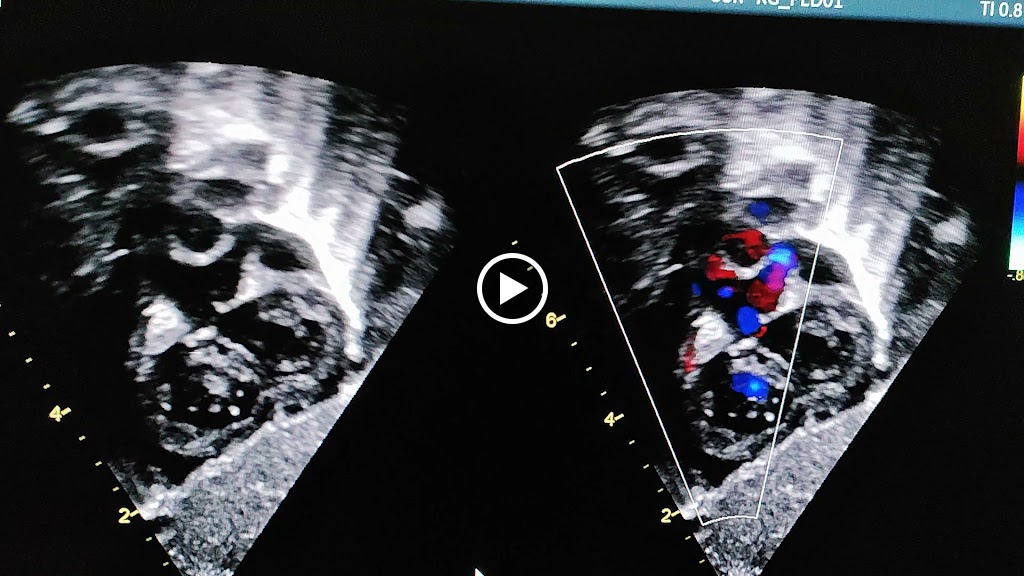

I was born and brought up in Jaunpur studied in St.John school siddiquepur jaunpur. Then later on i joined Allen Inistitute Kota for 1 year and got selected in AIPMT (NEET) with all my family and well wishers blessing. After which i did pediatric for 3 years and fellows in Pediatric Cardiology from Mumbai B J wadia hospital for Children and started my practice in Jaunpur as a consultant pediatric. We have all lasted equipment used for General Paediatric and Paediatric Cardiology patient management. Our staffs are very caring and dedicated towards patient management. We have all facilities like NICU, PICU, all latest VACCINATION, General/pvt wards and 2DECHO at very nominal prices compared to other hospitals along with quality care.

Office Gallery

Videos